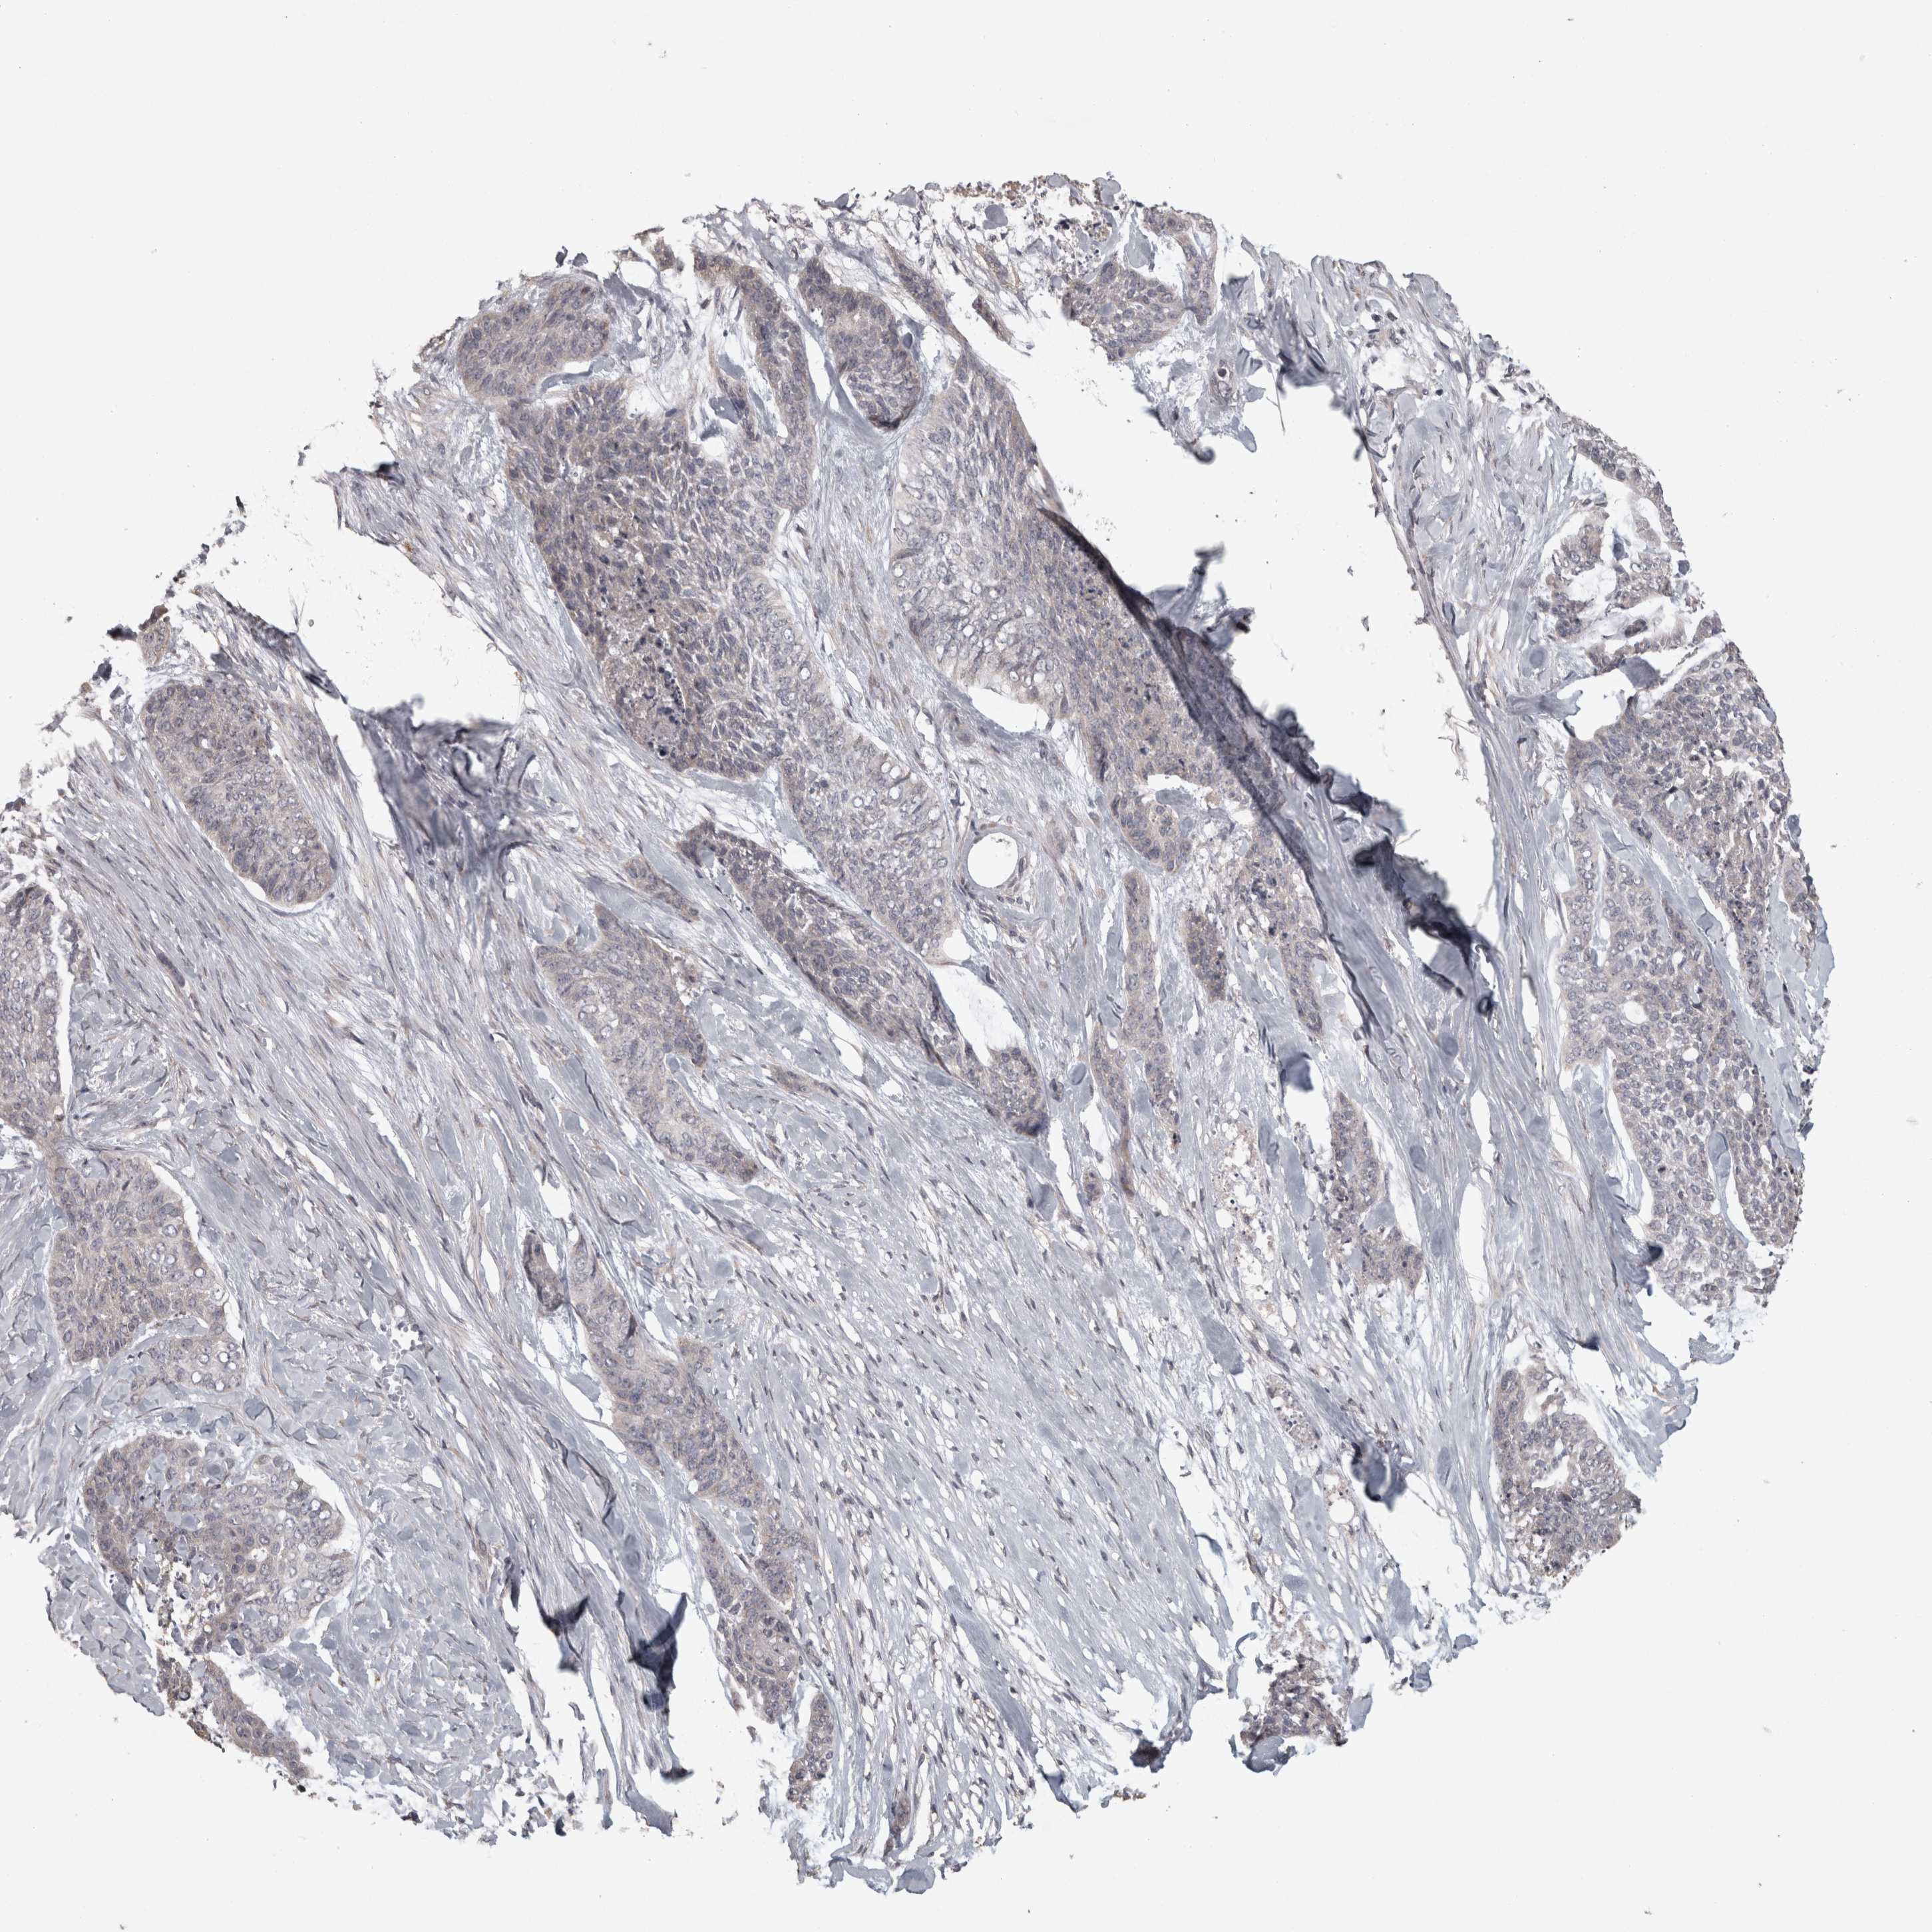

SKIN CANCER - Protein expressioni

A mouse-over function shows sample information and annotation data. Click on an image to view it in a full screen mode. Samples can be filtered based on level of antibody staining by selecting one or several of the following categories: high, medium, low and not detected. The assay and annotation is described here.

Antibody stainingi

Antibody staining in the annotated cell types in the current human tissue is reported as not detected, low, medium, or high, based on conventional immunohistochemistry profiling in selected tissues. This score is based on the combination of the staining intensity and fraction of stained cells.

Each image is clickable and will lead to virtual microscopy that enables deeper exploration of all samples and also displays staining intensity scores, fraction scores and subcellular localization as well as patient and tissue information for each sample.

Antibody HPA026303

Antibody CAB020822

Squamous cell carcinoma, NOS